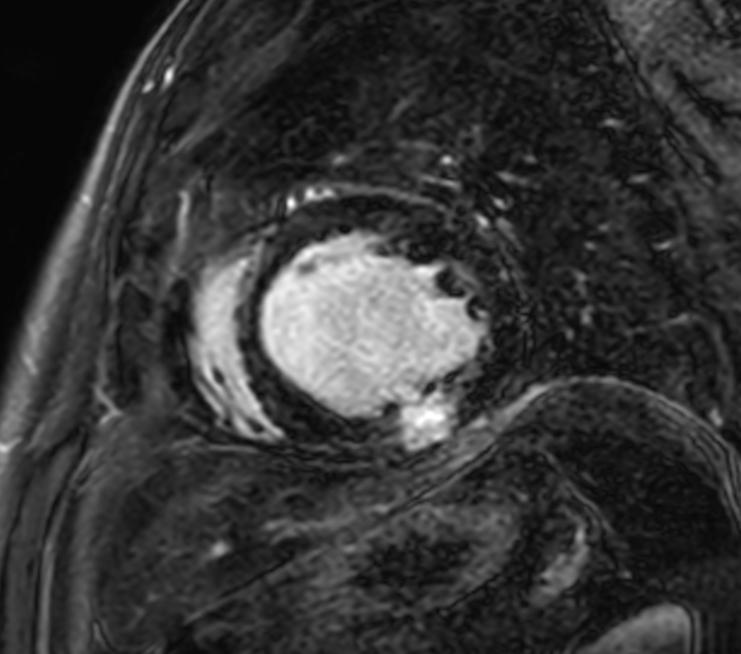

3D SPIR VI, short axis view